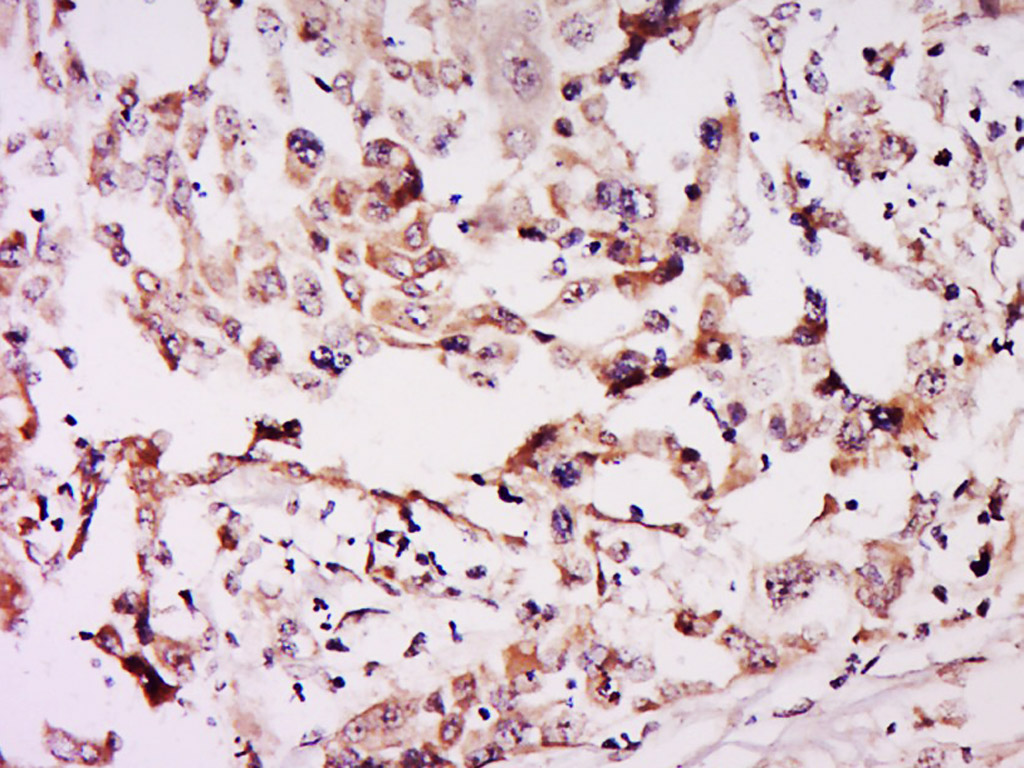

Tissue/cell: human breast cancer; 4% Paraformaldehyde-fixed and paraffin-embedded;

Antigen retrieval: citrate buffer ( 0.01M, pH 6.0 ), Boiling bathing for 15min; Block endogenous peroxidase by 3% Hydrogen peroxide for 30min; Blocking buffer (normal goat serum,C-0005) at 37∩ for 20 min;

Incubation: Anti-NSUN6 Polyclonal Antibody, Unconjugated(bs-19484R) 1:500, overnight at 4∑C, followed by conjugation to the secondary antibody(SP-0023) and DAB(C-0010) staining